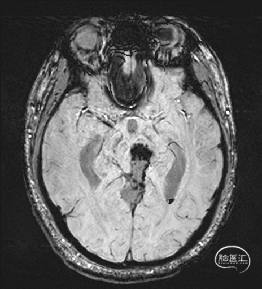

术前MRI检查

术前MRI检查提示左侧丘脑中脑海绵状血管瘤并卒中,梗阻性脑积水;

根据MRI及DTI显示,只有在丘脑与上丘之间的点(dot)进入病变才可能在切除病变时最大程度保护神经功能,由于上述原因,该“点”在术中显露极其困难,虽有导航指引,电生理监测的条件下,对术者的耐心、技术、经验及体能依然是极大的挑战;

本例患者磁共振检查清晰显示病变位于左侧丘脑中脑区域,且位于丘脑内下方向中脑顶盖延续,病变的上部、前部、外侧部都有重要的神经组织,因此,手术从上方、前方、外侧方向切除病变均难以实施;

从后方有POPPEN入路、Krause入路等,但是因为病变并未充分向松果体区、大脑大静脉后方突出,有大脑大静脉复合体的阻挡,POPPEN入路有较大的难度显露及切除病变,残留的可能性比较大;传统显微镜下进行的幕下小脑上入路在病变的显露及切除上依然有较大的难度。